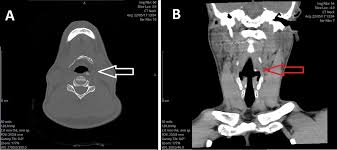

Most patients with symptoms of hyoid bone syndrome report pain radiating to the ear throat temple zygomatic arch temporomandibular joint TMJ mandibular molar teeth on the same side and a vertical axis of pain that runs from the temple superiorly down through the TMJ con- tinuing inferiorly to the clavicle and terminating in the middle of the breast without extending below the nipple Fig. How is Eagles syndrome diagnosed. Nonspecific cervical pain is a common complaint in primary ear nose and throat clinic patients.

According to an article in the official journal for the American Academy of Otolaryngology hyoid bone fractures usually cause symptoms such as difficulty swallowing and pain upon head rotation. All patients presented with throat pain and had tenderness of 1 63 or both 38 greater cornua of the hyoid bone. The pain starts below the angle of the mandible and radiates into the anterolateral neck.

4 In addition cerebrovascular ischemic events may occur due to the involvement of the carotid artery and jugular vein. Difficulty swallowing and talking.

33 The connections to the hyoid bone explain the radiating symptoms. The pain starts below the angle of the mandible and radiates into the anterolateral neck. Hyoid Bone Syndrome ES can have many symptoms in common. The most common symptom is point tenderness at the lateral aspect of the hyoid or superior cornu of the thyroid cartilage. A further syndrome relating to the hyoid bone the styl-ohyoid syndrome was reported by Shenoi 1972 with a specific finding of tenderness over the lesser cornu of the hyoid bone but very similar symptoms. Its those darn cranial nerves that get irritated make us hurt sometimes feel. Other symptoms of Eagle syndrome include. Hyoid bone syndrome is a type of cervicofacial pain that is caused by degeneration of the greater cornu of the hyoid at the attachment of the stylohyoid ligament. When it flares up even without pressing it often feels like someone has shoved forceps through my skin into the soft area behind my chin upwards toward my mouth and is pinching them closed around the skin and muscle etc between the points.